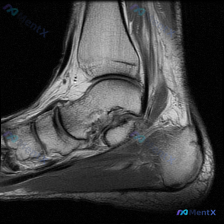

刚看到这个病例,临床提问是"影像中可见什么?",临床判断是存在软组织积液,我整理了完整的影像分析和临床思路分享给大家。 一、病例影像基础信息 这是一张踝关节MRI轴位T2序列单帧图像,先给大家整理影像读片结果: 1. 骨与关节:胫骨、腓骨远端形态正常,骨髓腔无异常信号,踝关节间隙清晰,未见骨质破坏、...